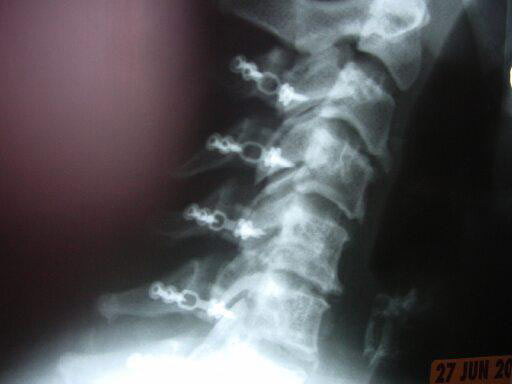

63 -year- old female with multilevel cervical myelopathy and stenosis.